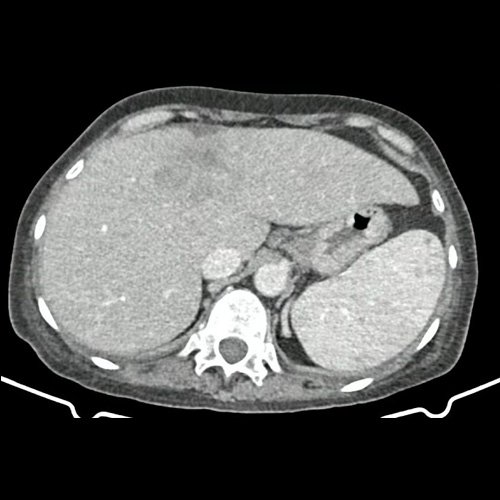

• TAC abdomen con contraste (un mes atrás): Múltiples estructuras ganglionares retroperitoneales, pre y lateroórticas, hiliares hepáticas y esplénicas aumentadas en número y de tamaño, de rango no megálico. El hígado es de forma, tamaño y situación habituales. Sus bordes son agudos. Se observa en segmento IV a –IVb, una lesión nodular hipodensa, ligeramente heterogénea, subcapsular, de bordes parcialmente definidos, con tendencia a homogeneizar con respecto al parénquima adyacente en fase de equilibrio. Mide 5,3 cm CC x 4 cm DT  x 3,7 cm AP. Hallazgos que podrían corresponder en primera instancia secundarismo hepático sin poder descartar otras etiologías. La vía biliar intra y extrahepática es de calibre conservado. La vesícula biliar es de forma, tamaño y situación normales, sin imágenes que sugieran la presencia de litiasis. Tener en cuenta que este método puede pasar por alto litiasis colesterínicas. Esplenomegalia homogénea. El eje esplenoportal es de calibre y trayecto conservado. El páncreas es de características normales. El conducto de Wirsung es de calibre conservado. Las glándulas adrenales son normales. Ambos riñones son de forma, tamaño y situación habituales. Sin evidencia de alteraciones calicopiélicas ni ureterales. La aorta, las arterias ilíacas primitivas, internas, externas y femorales, son de calibre y trayecto conservado. Trombos murales y calcificaciones parietales aortoiliacas. La vena cava inferior y las venas ilíacas primitivas, internas, externas y femorales son de calibre y trayecto conservados. Aisladas formaciones diverticulares en colon sigmoides, sin cambios inflamatorios al momento del examen. La vejiga escasamente replecionada, sonda balón en su interior. El útero es de forma, tamaño y situación conservada, en AVF, sin alteraciones densitométricas. No se observan alteraciones en topografía anexial. No se observa líquido libre ni neumoperitoneo Flebolitos pelvianos.

• TAC de abdomen y pelvis CC EV - informe preeliminar (Dia 30): En esta ocasión se observa hepatomegalia. Sus bordes son agudos. Continúa visualizándose de mayor tamaño, involucrando a casi la totalidad del segmento IV, una lesión nodular, de márgenes irregulares, hipodensa, ligeramente heterogénea, subcapsular, de bordes parcialmente definidos, Mide 9 cm CC x 6.5 cm DT x 5 cm AP (antes medía 5,3 cm CC x 4 cm DT x 3,7 cm AP). Actualmente se observa otra lesión nodular adyacente a la anterior descripta, en el segmento IVa/VIII, de similares características, que mide 3.5 cm DT x 3 cm AP, y otra en segmento IVa/II que mide 3 cm CC x 1.5 cm DT x 1 cm AP. Además se destacan otras dos lesiones, con similares características que las previas descriptas en segmento II que mide 19 mm DT x 15mm AP y en segmento VI que mide 14mm DT x 17mm AP. Hallazgos que podrían corresponder a secundarismo vs proceso infeccioso. Cotejar con datos clínicos de la paciente. Múltiples estructuras ganglionares retroperitoneales, pre y lateroórticas, hiliares hepáticas y esplénicas aumentadas en número y de tamaño, destacándose, en actual estudio,  una preaórtica derecha que mide 10 mm en su eje corto. En base pulmonar derecha se observan múltiples formaciones nodulares sólidas, irregulares, que realzan de manera heterogénea tras las administración de contraste E.V, como así también se observa otra de similares características en pulmón izquierdo en contacto con pericardio, la cual es la de mayor tamaño y mide 19 mm DT x 17mm AP. Hallazgos que obligan a descartar secundarismo pulmonar. Leve derrame pleural derecho. Hallazgos no visualizados en TC previa. Esplenomegalia que muestra densidad discretamente heterogénea, con algunas zonas de hiporrefuerzo de aspecto nodular. Trombos murales y calcificaciones parietales aortoiliacas. Aisladas formaciones diverticulares en colon sigmoides, sin cambios inflamatorios al momento del examen. Pequeña hernia inguinal epiploica izquierda, sin complicaciones agudas al momento del examen. Flebolitos pelvianos. Granuloma calcificado en TCS del glúteo izquierdo que mide 14mm. No se identifican alteraciones en las estructuras óseas visualizadas. Lesión osteoblásticas en cuerpo vertebral de L2.

TAC de abdomen y pelvis (internación previa)